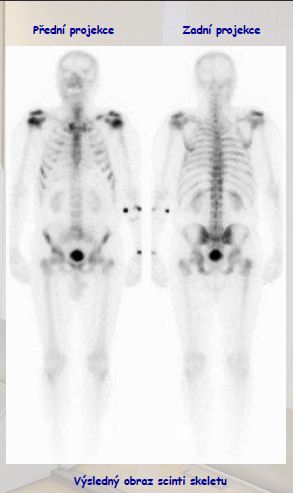

Scintigrafie skeletu

PřístrojM: dvouhlavá spect kamera PICKER

Radiofarmakum: 99mTc MEDRONAT (500-1000 MBq)

Postup vyšetření:

- intravenózní aplikace radiofarmaka – aktivita dle váhy pacienta

- kumulace 2-3 hodiny

- snímání ve dvou projekcích – přední/zadní

- poloha vleže na zádech (cca 20 minut)